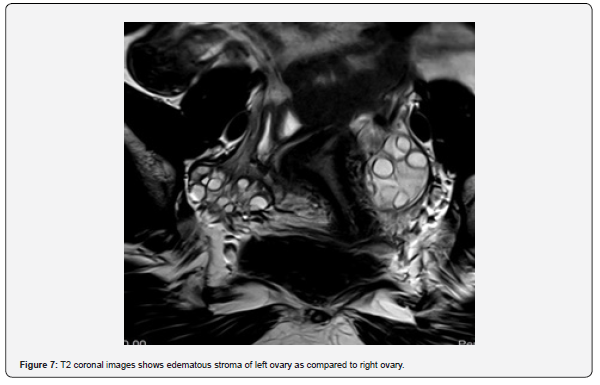

The patient is a 12-year-old girl who presented to emergency department with severe left-sided abdominal pain associated with persistent vomiting for the past two days. On physical examination left flank tenderness was noted with radiation to suprapubic area, there was no diarrhea or fever. Pelvic ultrasound with Doppler demonstrated bilaterally enlarged ovaries with small follicles with a markedly enlarged left ovary showing reduced vascularity and no evidence of identifiable ovarian cyst (Figures 1-4). Magnetic resonance imaging (MRI) demonstrated bilateral ovarian enlargement with multiple small follicles, assuming polycystic ovarian morphology. The left ovary was significantly enlarged, positioned posterior to the uterus and showed stromal edema with decreased post-contrast enhancement compared to contralateral side, findings consistent with ovarian torsion (Figures 5-10).

This finding demostrates the limitations of imaging in detecting small or subtle ovarian lesions and highlights the importance of clinical judgement together with supportive imaging findings when evaluating suspected ovarian torsion. Polycystic ovarian morphology in pediatric patients should also be considered a potential risk factor for ovarian torsion, even when a dominant cyst is not present. Additionally, MRI demonstrated bilateral polycystic ovarian morphology, with greater enlargement of the affected ovary. Increased ovarian volume associated with polycystic morphology has been reported as a possible predisposing factor for ovarian torsion. In this case, asymmetric ovarian enlargement in the setting of polycystic morphology may have increased the susceptibility of the affected ovary to torsion.